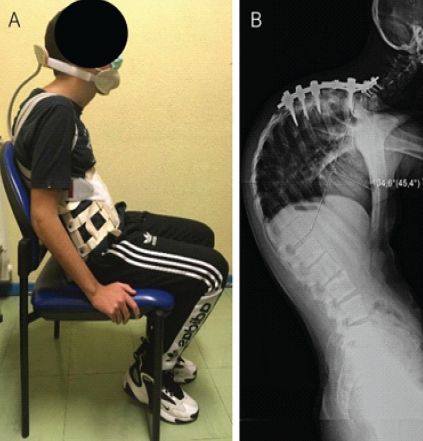

Eleven months after the index procedure, a revision surgery was performed, extending the fixation to the cervicothoracic junction (C5–T5) and removing the distal thoracolumbar instrumentation. Three weeks later, the patient developed signs of acute post-operative infection. Cultures confirmed Staphylococcus aureus (methicillin-sensitive), which was successfully managed with a 3-week course of intravenous flucloxacillin, surgical debridement and wound revision, followed by 10 weeks of oral cotrimoxazole and rifampin. Despite infection resolution, subsequent follow-up radiographs demonstrated recurrent and rapidly progressive thoracic kyphosis, with a Cobb angle increasing to 134°, indicating structural failure and loss of reduction at previously instrumented levels. Before surgical reintervention, a cervico-thoraco-lumbo-sacral orthosis – Milwaukee brace – was prescribed to provide external support and attempt to control further deformity progression (Fig. 4). Six months after the revision procedure, a third operation was performed, during which halo-gravitational traction was applied for 3 weeks with progressive loading from 5 to 10 kilograms (Fig. 5).

Figure 4: (a) Examination showing Milwaukee brace providing external support and (b) full-length lateral spine radiograph with a thoracic kyphosis measured at 134°.

Figure 5: (a) Clinical picture at evaluation of patient with halo-gravitational traction and (b) full-length lateral radiograph of the spine demonstrating severe thoracic kyphosis with a Cobb angle measurement of 132°.